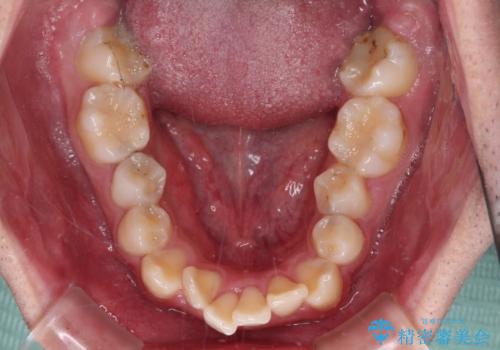

- 口元の突出感と奥歯の咬み合わせの悪さを気にして来院された患者様です。

口元はやや突出感があったため、上下左右の第一小臼歯4本を抜歯してワイヤー矯正にて抜歯矯正を行うこととしました。

また、左右ともに最後臼歯が交叉咬合になっており、外側に飛び出している上顎の最後臼歯を補助装置を利用して、積極的に内側に引き込むようにしました。